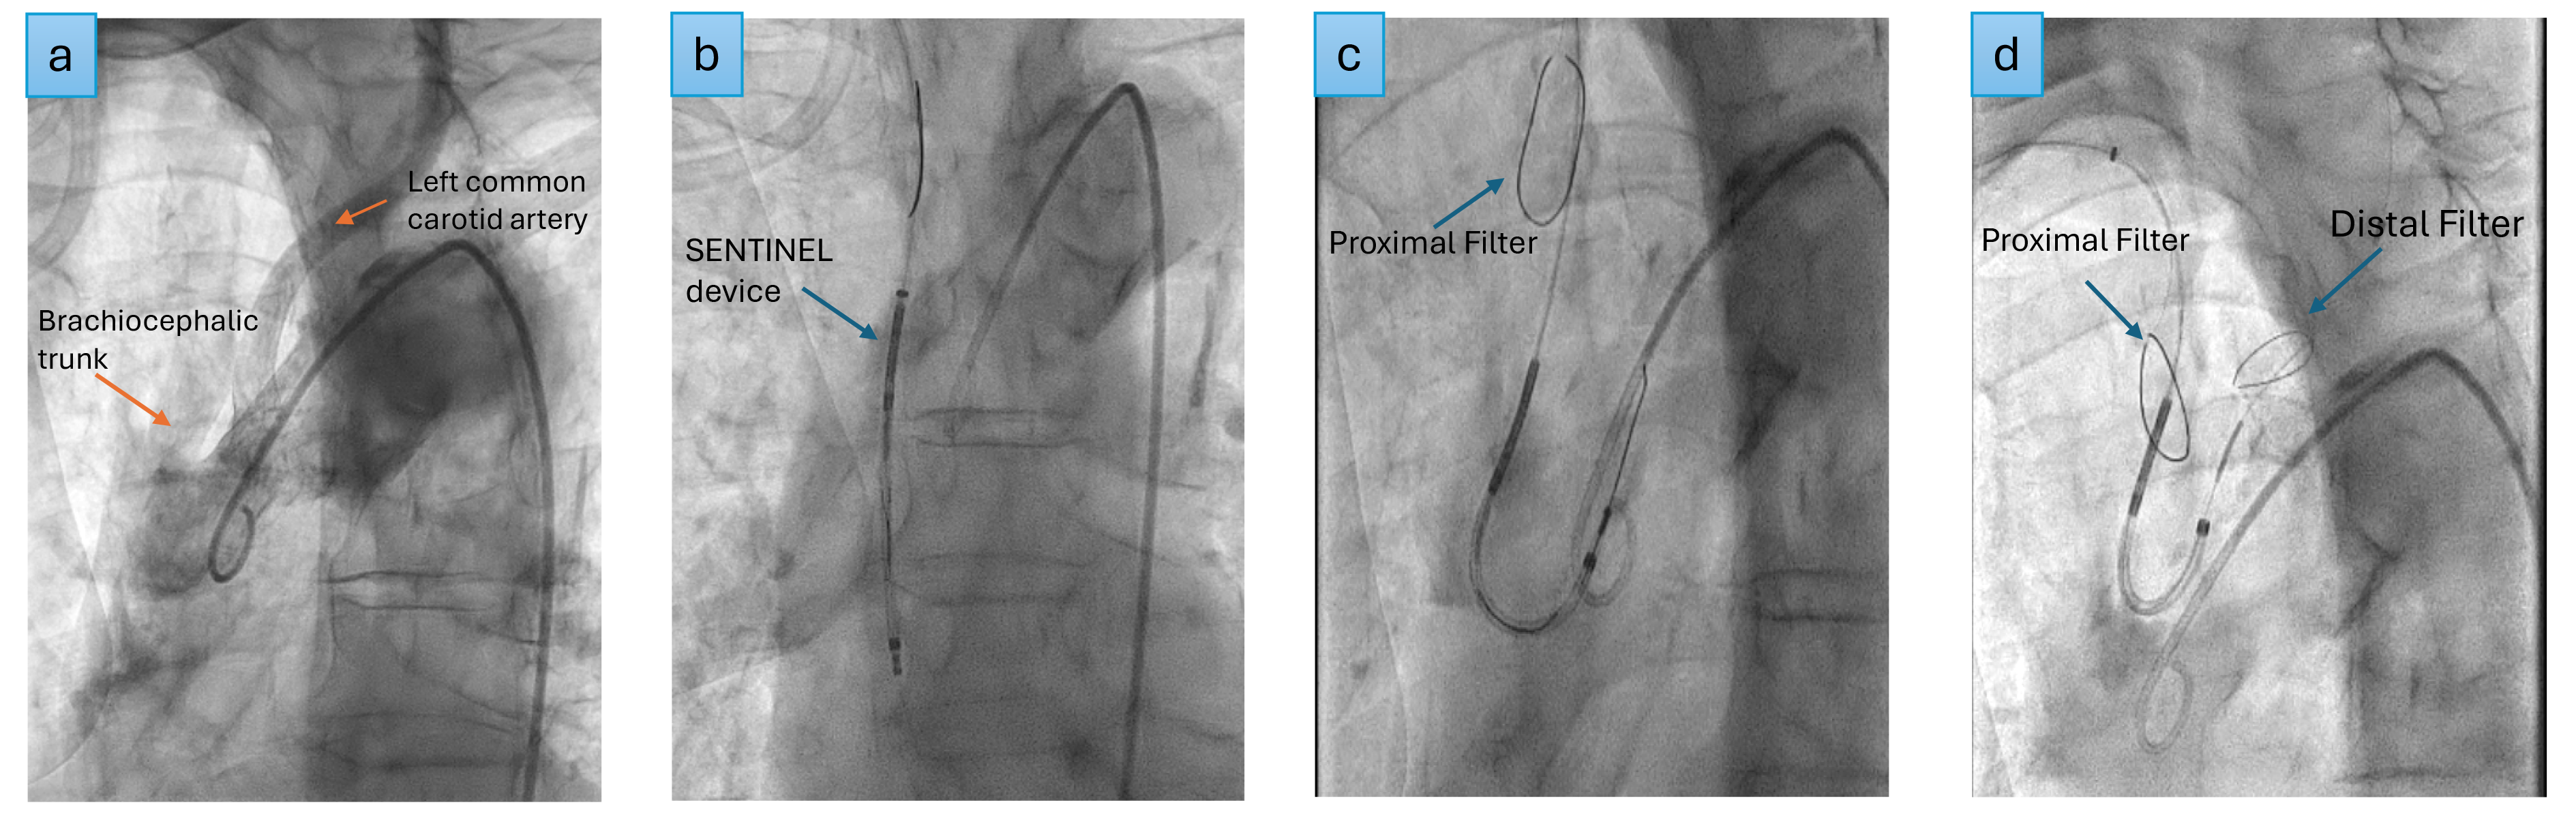

The SENTINEL (Boston Scientific, USA) remains the most commonly used and widely investigated CEP device (Fig. 3).

Fig. 3. SENTINEL deployment. (a) Aortogram, (b) SENTINEL device inserted over the guide wire into the ascending aorta, (c) proximal filter deployed in the brachiocephalic trunk, (d) distal filter deployed in the left common carotid artery.

The PROTECTED TAVR represents an RCT comparing 1501 patients with SENTINEL to 1499 patients without the device, finding no significant difference in the incidence of stroke within 72 hours (2.3% CEP vs. 2.8% control, 95% CI: –1.7 to 0.5) or in the risk of mortality [73]. However, debilitating strokes occurred in fewer patients in the CEP group than in the control group (0.5% CEP vs. 1.3% in the control group, 95% CI: –1.5 to –0.1). This may be attributed to the device capturing larger particles while smaller particles continue to escape the device, causing non-disabling strokes [9].

The CLEAN TAVI RCT, which used DW-MRI, also confirmed no significant reduction in stroke rates in the SENTINEL device arm compared to the control arm. Instead, it revealed equivalent lesion distribution on MRI; however, the lesion volume was lower in the CEP group [10]. The clinical relevance of a lower lesion volume is unclear.